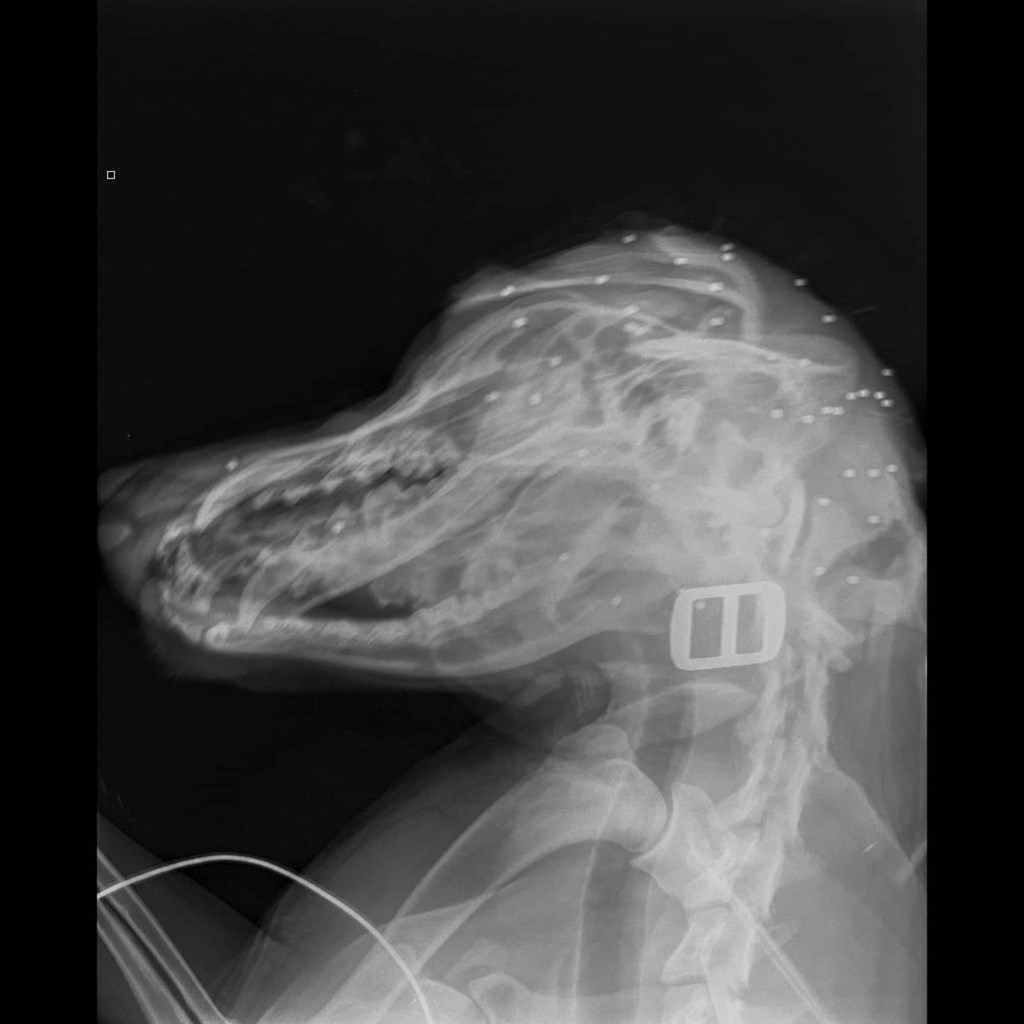

Χάρη στην άμεση κινητοποίηση της οικογένειας, ο σκύλος, που δέχτηκε τριάντα σκάγια στο κεφάλι, θα επιζήσει, ενώ σε βάρος του άνδρα που πυροβόλησε το άτυχο ζώο υπεβλήθη μήνυση.

«ΔΥΣΤΥΧΩΣ ΕΧΟΥΜΕ ΠΥΡΟΒΟΛΙΣΜΟ ΣΚΥΛΙΟΥ ΣΤΗΝ ΠΟΛΗ ΤΟΥ ΡΕΘΥΜΝΟΥ. Ο ΣΚΥΛΑΚΟΣ ΕΙΝΑΙ Ο ΑΡΗΣ, ΕΝΑΣ ΜΕΓΑΛΟΚΟΥΤΑΒΙΝΟΣ 9 ΜΗΝΩΝ, ΠΟΥ ΕΠΑΙΖΕ ΜΕ ΤΑ ΔΥΟ ΜΙΚΡΑ ΠΑΙΔΙΑ ΤΗΣ ΟΙΚΟΓΕΝΕΙΑΣ ΜΕΣΑ ΣΤΗΝ ΑΥΛΗ ΤΟΥ ΣΠΙΤΙΟΥ ΤΗΣ ΟΙΚΟΓΕΝΕΙΑΣ ΤΟΥ, Η ΟΠΟΙΑ ΕΙΝΑΙ ΠΕΡΙΚΛΕΙΣΤΗ. ΤΟ ΖΩΟ ΒΛΗΘΗΚΕ ΜΕ ΠΥΡΟΒΟΛΟ ΟΠΛΟ ΑΠΟ ΕΝΑΝ ΑΝΔΡΑ, ΥΠΑΛΛΗΛΟ ΔΙΠΛΑΝΗΣ ΕΤΑΙΡΕΙΑΣ, ΠΟΥ ΤΟ ΠΥΡΟΒΟΛΗΣΕ ΣΤΟ ΚΕΦΑΛΙ ΑΚΡΙΒΩΣ ΕΞΩ ΑΠΟ ΤΟΝ ΜΑΝΤΡΟΤΟΙΧΟ ΤΗΣ ΑΥΛΗΣ ΤΟΥ ΣΠΙΤΙΟΥ, ΚΑΙ ΤΗΝ ΣΤΙΓΜΗ ΠΟΥ ΤΑ ΔΥΟ ΠΑΙΔΑΚΙΑ ΗΤΑΝ ΔΙΠΛΑ ΣΤΟ ΖΩΑΚΙ. Ο ΑΡΗΣ ΕΧΕΙ ΤΡΙΑΝΤΑ ΣΚΑΓΙΑ ΣΤΟ ΚΕΦΑΛΙ, ΑΛΛΑ ΛΟΓΩ ΤΗΣ ΓΡΗΓΟΡΗΣ ΑΝΤΙΔΡΑΣΗΣ ΤΗΣ ΟΙΚΟΓΕΝΕΙΑΣ ΚΑΙ ΤΩΝ ΦΩΝΩΝ ΤΩΝ ΣΟΚΑΡΙΣΜΕΝΩΝ ΠΑΙΔΙΩΝ, ΜΕΤΑΦΕΡΘΗΚΕ ΑΜΕΣΑ ΣΤΟ ΚΤΗΝΙΑΤΡΟ ΚΑΙ ΘΑ ΕΠΙΖΗΣΕΙ. Ο ΚΑΚΟΠΟΙΗΤΗΣ ΤΟΥ ΑΡΗ ΕΙΝΑΙ ΓΝΩΣΤΟΣ ΚΑΙ ΑΥΡΙΟ ΤΟ ΠΡΩΙ ΘΑ ΚΑΤΑΤΕΘΕΙ ΜΗΝΥΣΗ ΕΝΑΝΤΙΟΝ ΤΟΥ ΣΤΗΝ ΕΙΣΑΓΓΕΛΙΑ ΠΡΩΤΟΔΙΚΩΝ ΡΕΘΥΜΝΟΥ, ΚΑΘΩΣ ΠΡΟΚΕΙΤΑΙ ΓΙΑ ΑΤΟΜΟ ΕΠΙΚΙΝΔΥΝΟ, ΠΟΥ ΠΥΡΟΒΟΛΕΙ ΧΩΡΙΣ ΝΑ ΤΟΝ ΝΟΙΑΖΕΙ ΓΙΑ ΤΑ ΖΩΑ Ή ΤΟΥΣ ΑΝΘΡΩΠΟΥΣ ΓΥΡΩ ΤΟΥ. ΘΕΩΡΩ ΟΤΙ ΑΠΟ ΤΥΧΗ Η ΣΦΑΙΡΑ Ή ΤΑ ΣΚΑΓΙΑ ΔΕΝ ΧΤΥΠΗΣΑΝ ΚΑΝΕΝΑ ΑΠΟ ΤΑ ΔΥΟ ΠΑΙΔΑΚΙΑ, ΕΝΩ Ο ΣΚΥΛΑΚΟΣ ΕΙΝΑΙ ΕΠΙΣΗΣ ΤΥΧΕΡΟΣ ΠΟΥ ΕΦΑΓΕ ΜΟΝΟ ΔΙΑΣΠΟΡΑ ΑΠΟ ΣΚΑΓΙΑ ΚΑΙ ΟΧΙ ΤΗΝ ΣΦΑΙΡΑ ΣΤΟ ΚΕΦΑΛΙ, ΑΝ ΚΑΙ ΝΟΜΙΖΩ ΟΤΙ ΤΟ ΚΕΦΑΛΙ ΤΟΥ ΣΚΥΛΙΟΥ ΠΡΕΠΕΙ ΝΑ ΗΤΑΝ Ο ΣΤΟΧΟΣ ΤΟΥ ΥΠΟΨΗΦΙΟΥ ΦΟΝΙΑ», γράφει στη λεζάντα της ανάρτησης του χρήστη που το δημοσιοποίησε μέσω Facebook.